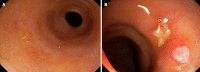

Figures